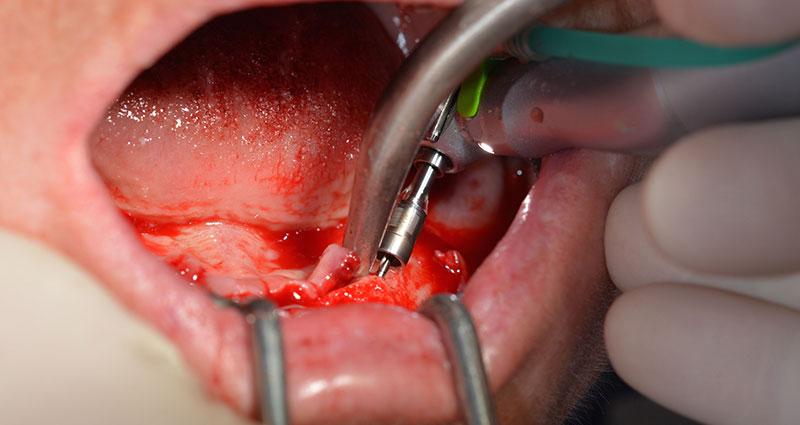

Le trou mentonnier doit d'abord être identifié comme une structure anatomique limitante, puis l'os cortical de la crête a été régularisé avec une pièce à main droite et une fraise sphérique de grande taille (Fig. 4).

Dentition résiduelle

Fig. 4

Le protocole chirurgical préconisé pour les implants utilisés (SKY, Bredent Medical) précise une vitesse de rotation de 1.200 tr./min. pour le pré-forage (Fig. 7 - 9).

Vitesse de 1.200 tr./min.

Ceci correspond à la position suivante prédéfinie dans l'Implantmed. Nous voyons ici le contre-angle W&H tenu à un angle de 45° par rapport à la crête dans la région de 45 afin de préserver le nerf mentonnier. Le trou mentonnier sert de repére anatomique à tous les forages de cette région. Les forages suivants ont été effectués à la vitesse réduite de 300 tr./min. (Fig. 10 et 11).

Contre-angle W&H

Fig. 10

Vitesse de 300 tr./min.

Fig. 11